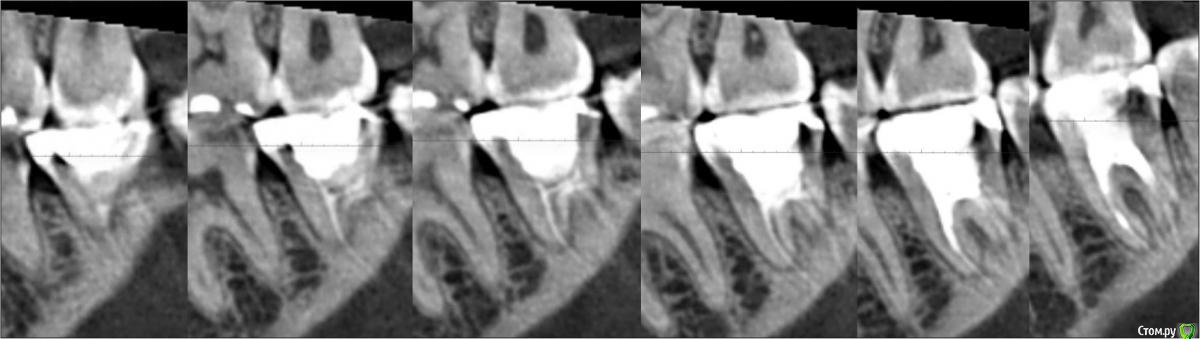

Ms.Olgin Опубликовано 15 марта, 2018 Поделиться Опубликовано 15 марта, 2018 (изменено) Доброго времени суток, уважаемые доктора, помогите разобраться с вопросом, который указан в теме. В кратции - у депульпированного зуба (7ой нижний) откололся кусочек. Я естественно сходила на консультацию - врач осмотрела зуб, постучала по нему, по скребла и отправила на 3D снимок (фото прикрепила). По результатам снимка предложила мне один единственный вариант - вкладку. Мне естественно стало интересно что это за вкладка,и я почитала информацию в том числе и на этом форуме, и... сейчас я вообще запуталась. И не вижу никаких преимуществ в кладки в моем случае перед коронкой, кроме как заплатить в 2 раза больше клинике за "лечение". Наверно пойду ще к одному врачу на консультацию...но хотелось бы услышать здесь мнения, буду очень благодарна Изменено 15 марта, 2018 пользователем Ms.Olgin Ссылка на комментарий

M@estro Опубликовано 15 марта, 2018 Поделиться Опубликовано 15 марта, 2018 Здравствуйте! Насколько можно судить по снимку, вкладку ставит в зуб нет необходимости. По срезу не видно апикальной части зуба - если там нет признаков воспаления, то нужно поменять пломбу в культевой части зуба, убрав кариес, и покрыть зуб коронкой. Ссылка на комментарий

Ms.Olgin Опубликовано 16 марта, 2018 Автор Поделиться Опубликовано 16 марта, 2018 (изменено) Здравствуйте! Насколько можно судить по снимку, вкладку ставит в зуб нет необходимости. По срезу не видно апикальной части зуба - если там нет признаков воспаления, то нужно поменять пломбу в культевой части зуба, убрав кариес, и покрыть зуб коронкой. Спасибо за ответ! По ощущениям - ничего не беспокоит. Она смотрела снимок, и я насколько поняла, каналы чистить в моем случае не будет..сказала хорошо запломбированы.,но я ещё наверно позвоню уточню этот момент. Я больше переживаю что у меня под этой вкладкой зуб расколется, он же мертвый, коронка, как мне кажется надёжнее будет... Изменено 16 марта, 2018 пользователем Ms.Olgin Ссылка на комментарий